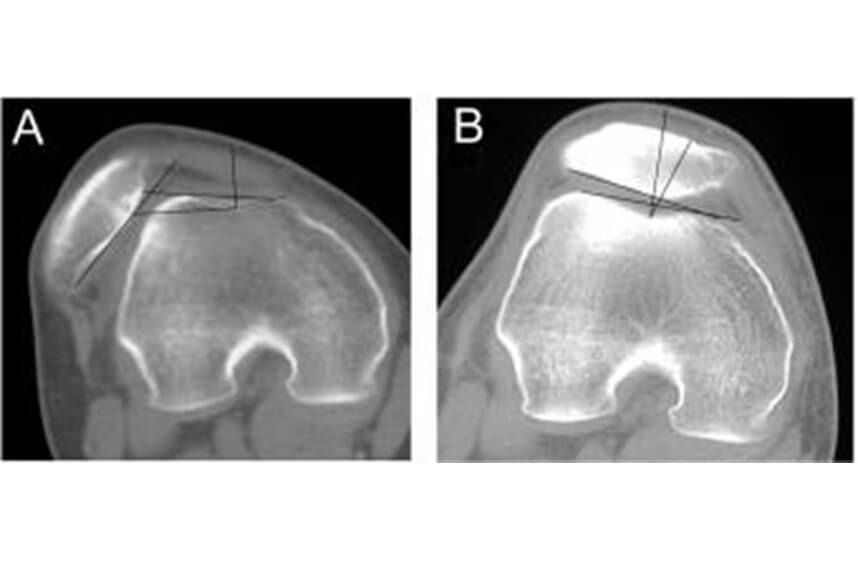

- Patellofemoral Syndrome

This condition causes pain felt in the back of the knee and, in severe cases, can lead to patellar dislocation.

The knee is an extremely complex joint, and a slight alteration in the form or function of a muscle group – in this case, the quadriceps – can create increased pressure on the patella, leading to pain, sprain, or even dislocation if the patella moves out of place.

This condition can generally be treated through kinesitherapy in most cases. When the patient has experienced repeated patellar dislocations, surgical intervention is required for fixation. Our proposed kinesitherapy program aims to rebalance the musculo-ligamentous structure of the knee and increase its resistance, so it can handle daily demands.